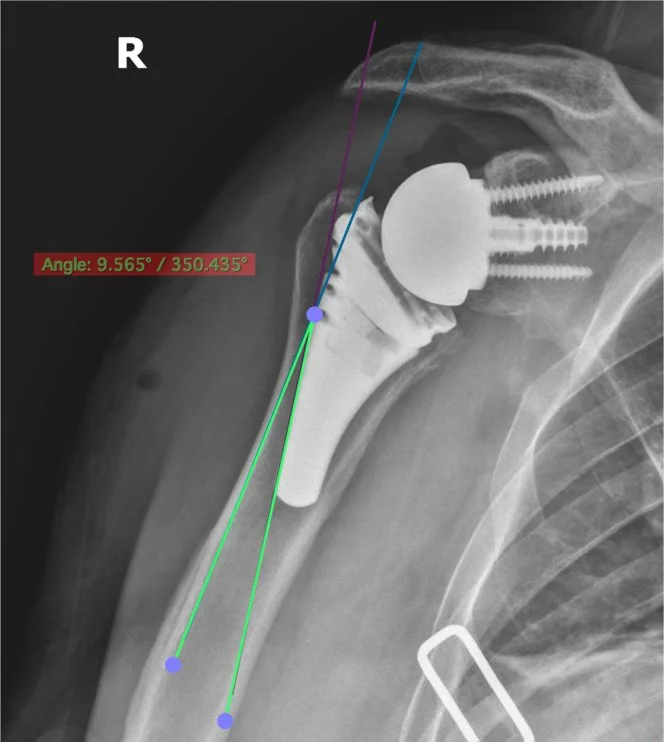

Figure 2 - Initial postoperative radiograph demonstrating a stem that was placed into valgus alignment. Note the difference of more than 9° between the alignment of the prosthesis and humerus.

Figure 4 - Initial postoperative radiograph demonstrating a stem that was placed into neutral alignment. Note the difference of less than 5° between the alignment of the prosthesis and humerus. The varus/valgus is calculated by drawing a line that is in line with the lateral aspect of the implant and a separate line that goes along the lateral border of the humerus. The angle between these 2 lines is the amount of varus/valgus that the implant is in.